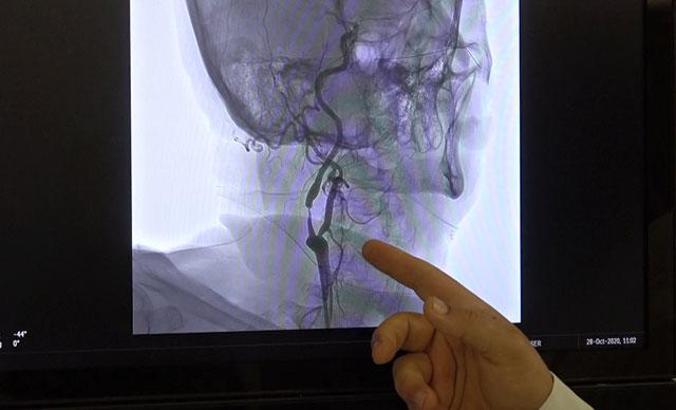

Prof. Dr. Zülfikar Arlıer, beyin damarının yırtılmasına bağlı, beynin kafatası ile iç zarı ya da iç zar ve beyin arasında olabilen beyin kanamalarının ameliyatla tedavi edilebildiğini ancak baloncuķ veya doğumsal damar bozukluklarının ilerleyen teknolojiyle ameliyata gerek kalmadan anjiyo yöntemiyle önlenebildiğini belirtti. Prof. Dr. Arlıer, felç nedenleri arasında olan ve bir tarafta uyuşukluk, karıncalanma, kuvvetsizlik, baş ağrısı, bulantı, kusma gibi şikayetlerle belirti veren beyin kanamalarının çeşitli nedenlerle kan sulandırıcı kullanan hastalarda daha ağır tablolar oluşturduğuna dikkat çekti.

"Beyin kanamaları genellikle tansiyon, travma, tümör, baloncuk gibi durumlar ya da genetik olarak beyin damarlarının zayıf olmasına bağlı zamanla yırtılmasıyla oluşan kanamalardır. Eğer tansiyona bağlı bir durum ise tansiyonun ayarlanması, diyet yapılması, tuzsuz beslenilmesiyle önlenebilir. Beyin damarlarının zayıflamasıyla oluşan baloncuk dediğimiz kanamalarda ise MR, tomografi gibi filmlerle önceden tespit edilebilirse ameliyat ya da anjiyo yöntemiyle kasıktan girilip, beyin damarındaki o baloncuğun ya da bozuk damarların içi özel maddelerle doldurularak önlenebilir. Genetik olarak zayıf ya da karmaşık damar yapısına bağlı kanamalar da ameliyatla veya anjiyo yöntemiyle yine kapatılarak o damarlardaki basınçlar düşürülüp kanama önlenebilir."

"Özellikle baloncuk ya da doğumsal damar bozukluklarından kaynaklı kanamalar, daha önceden tespit edilemiyordu ya da ameliyat dışında başka hiçbir çözüm yoktu ama günümüzde artık teknolojik gelişmelerle beyni açmadan, kasıktan girilerek o damarlara kadar ulaşıp özel sıvı veya özel maddelerle damar tedavi edilerek önlenebiliyor. Bu son 10-15 yılın teknolojisi ama her geçen gün gelişen bir teknoloji. Özellikle son 5 yılda ameliyattan ziyade uygun damarlarda anjiyo ile kapatma yöntemleri ön planda."